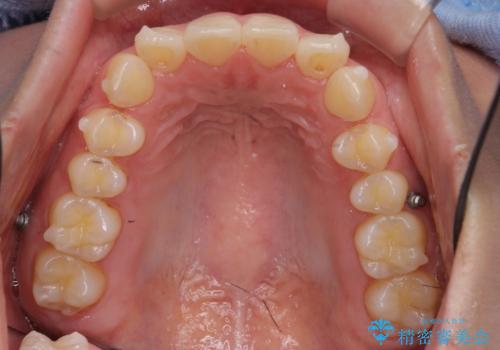

- インビザライン、ワイヤー矯正併用

- 前歯のガタつきと、下の前歯が一本短いことを主訴に来院。

インビザラインのマウスピースではめる装置で歯を引っ張り出すことは難しいと説明し、下の前歯だけワイヤー部分矯正を行ってからインビザライン矯正で仕上げをしました。